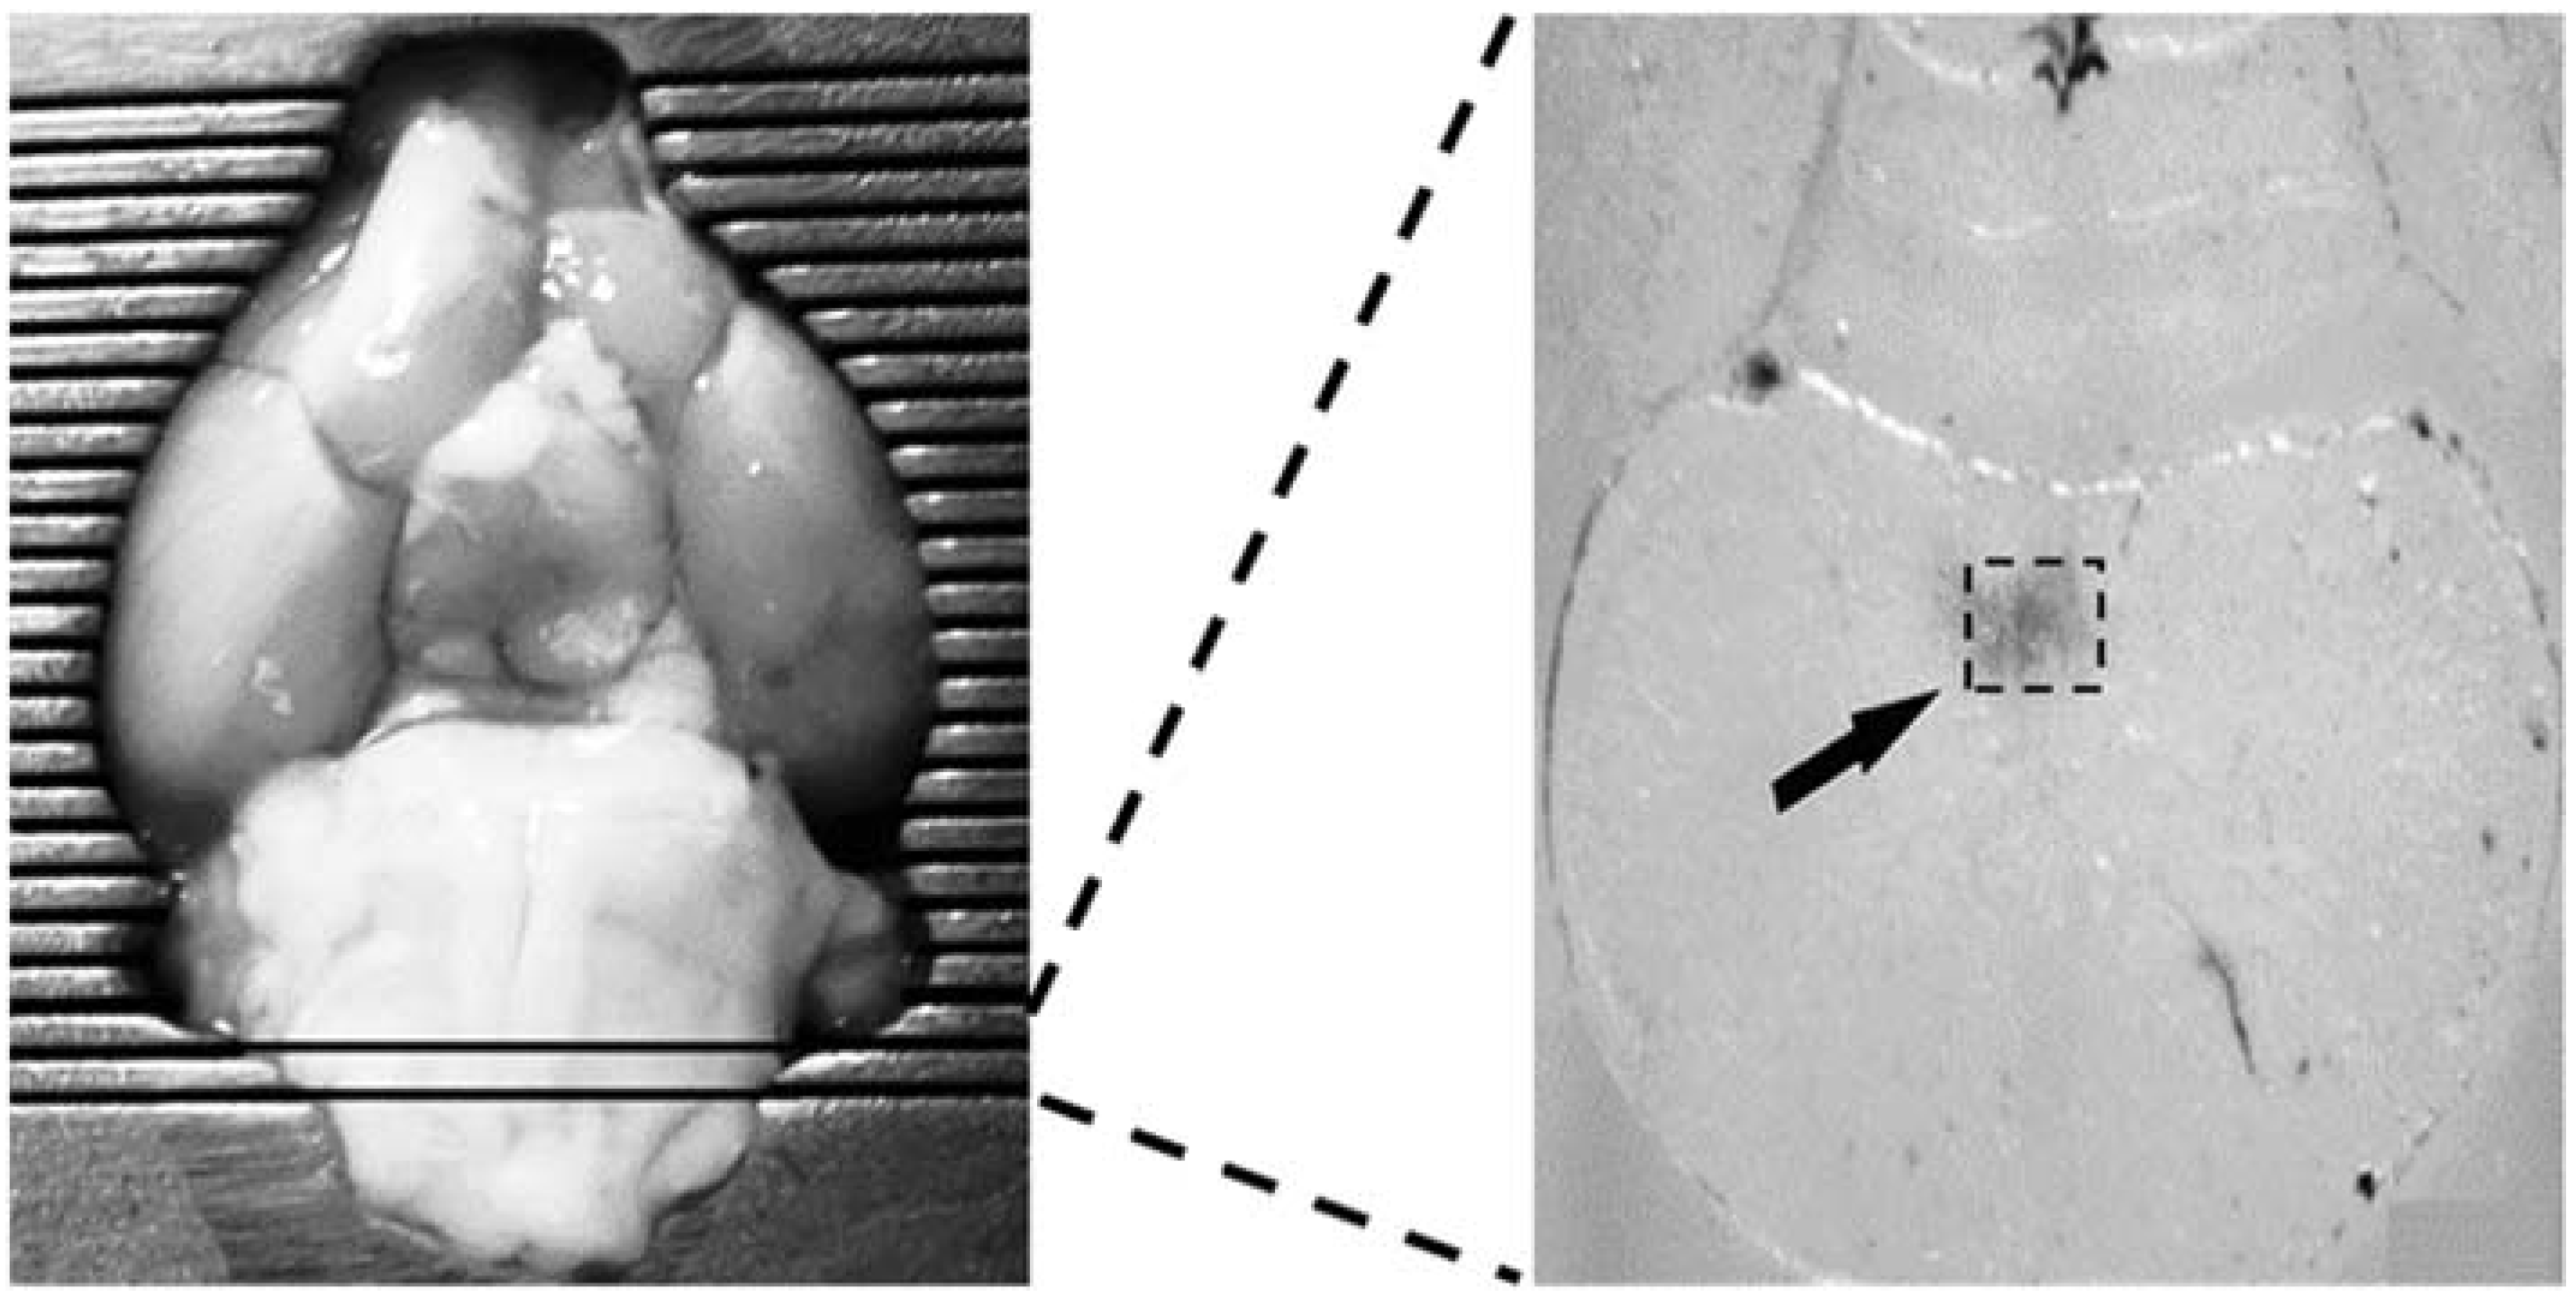

2.5. Isolated Carotid Sinus Preparation, Carotid Chemoreceptors Stimulation and BGR Measurement